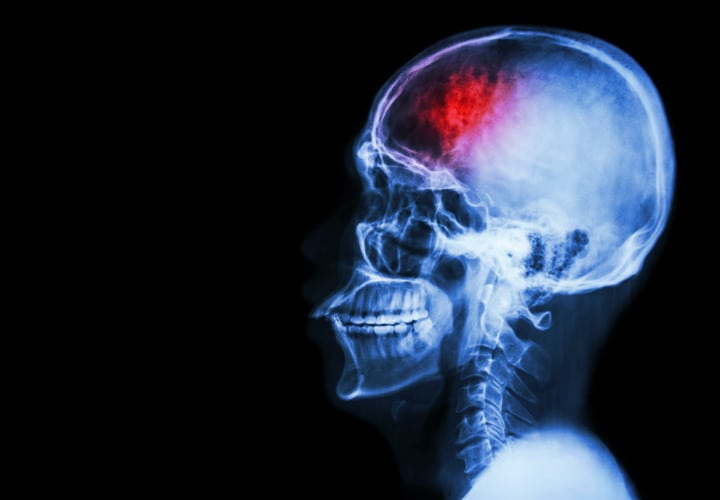

¿QUÉ ES LA MIGRAÑA?

Es un dolor de cabeza pulsátil e intenso que habitualmente afecta a un lado de la cabeza, aunque puede afectar a ambos. El dolor empieza repentinamente y puede estar acompañado de síntomas visuales, neurológicos o gastrointestinales.